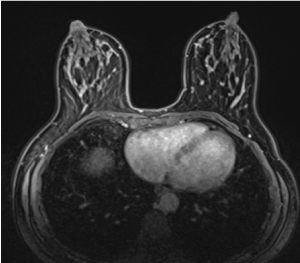

A 42-year-old female with a family history of breast cancer consulted complaining of skin changes on the right breast erythema and scaling with nipple serohematic discharge (Figure 1). There was no palpable breast masses nor lymphadenopathy. Ultrasound, mammography, and magnetic resonance were performed and a well-circumscribed nodule in the upper external quadrant was found, categorized as BI-RADS 4A (Figure 2). The nodule biopsy demonstrated, a fibroadenoma. Incisional biopsy of the nipple showed cells in the epidermis with abundant clear cytoplasm, big nuclei with granular chromatin, and prominent nucleoli (Figure 3). Immunohistochemistry demonstrated positive epithelial membrane antigen (EMA) and cytokeratin 7 (CK7) with negative p63 and HMB-45. Therefore, the patient was diagnosed with a mammary Paget disease (MPD).

Figure 2. MRI Showed a 7-mm mass in the upper external quadrant of the right breast, which was biopsied and diagnosed as a fibroadenoma